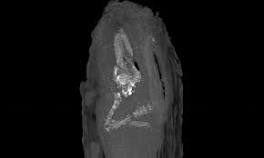

Imaging technology of tiny coffin demonstrates the value ancient Egyptians "placed on life even in ... Thanks once again to modern imaging technology [computed tomography], researchers looked inside a tiny wooden coffin and saw a baby, no more ...